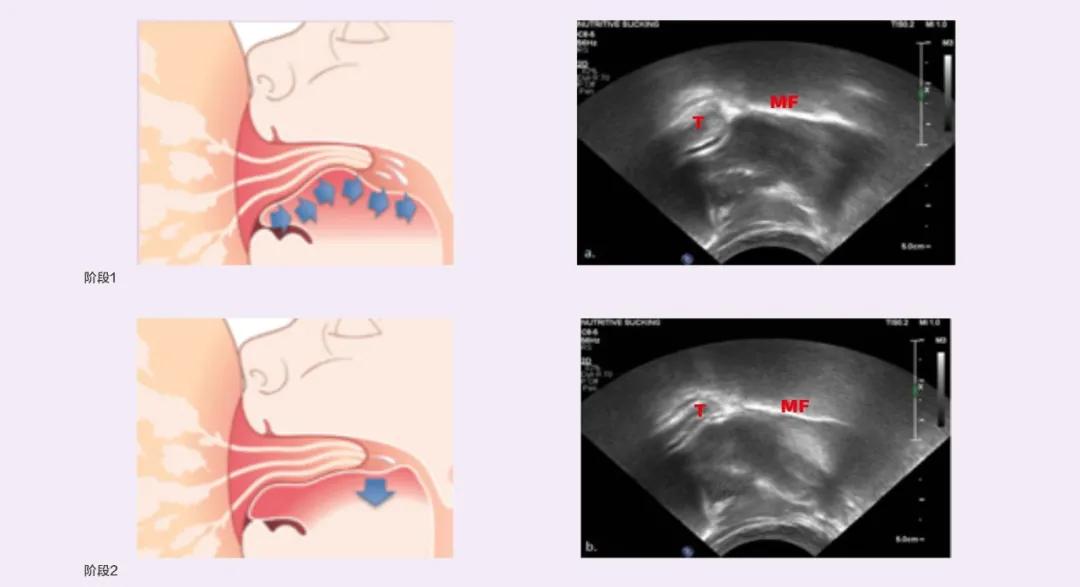

飞利浦新安怡,通过前沿的3D超声技术,观察和研究婴儿的吮吸动作,高度模拟宝宝的自然吮吸,从而促进产品技术研发和设计创新,达到更舒适、高效的泌乳体验。同样,通过 前瞻性研究婴儿的营养性吸吮,这被认为是最复杂的婴儿期活动之一,也是中枢神经系统完整性的重要指标 ,从而更好地为婴儿有效喂养提供科学支持。

超声研究母乳喂养期间宝宝舌头运动模式

在吸乳器的研发过程中,飞利浦新安怡一直坚信“ 宝宝是最好的泌乳专家 ”,婴儿吮吸时母乳呈喷射状自然涌出,分泌大量乳汁,飞利浦新安怡科学还原这一原理,研发的双边电动吸乳器采用了特别设计的亲吮按摩垫。

飞利浦新安怡双边电动吸乳器能够模拟宝宝的两段式吮吸规律,46秒获得奶阵,16分钟内轻松完成吸乳[5]。第一阶段快而浅,按摩产生喷乳反射;第二阶段慢而深,深度排空。原生快吸科技加持,为每一个在亲喂路上披荆斩棘的妈妈省时省力。